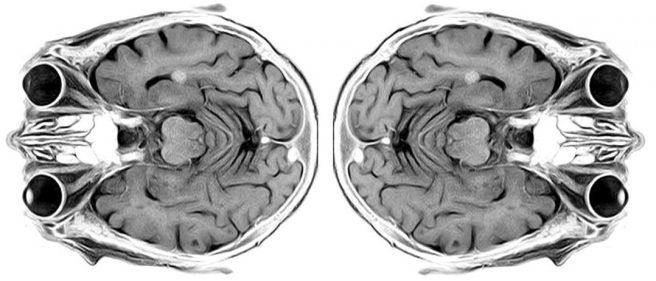

- Researchers report that while two genetic forms of Parkinson’s (LRRK2- & GBA-associated PD) express the same disease-specific networks as iPD, information flow through these networks differs profoundly across the patient groups. They “applied graph theory to metabolic brain imaging to understand the effects of genotype on the organization of previously established PD-specific networks”. They recruited 14 cases of LRRK2-associated PD, 12 GBA-associated PD, 14 idiopathic PD & 14 controls. LRRK2-associated Parkinson’s exhibited increased functional connectivity within the metabolically active PD-related pattern core zone. By contrast, GBA-associated PD gains in connectivity extend outside the core – could this correlate with more aggressive phenotype? (Click here to read more about this).